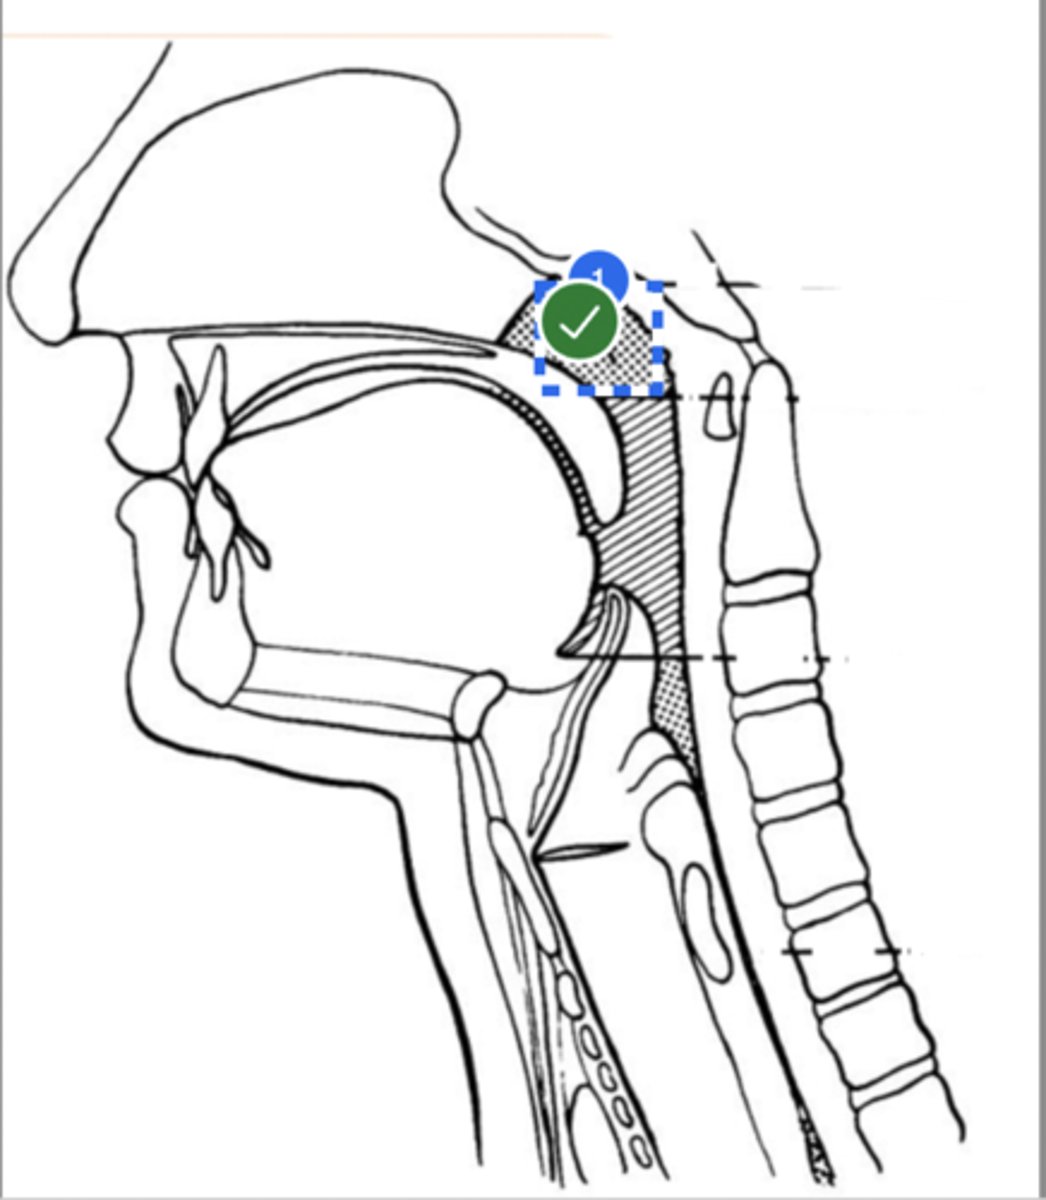

Label base of tongue (lateral view)

label anterior tongue (lateral view)

Label posterior/ back of tongue (lateral view)

Label Mandible (lateral view)

Label velum/ soft palate (lateral view)

Label hyoid bone (lateral view)

Label epiglottis (lateral view)

Label thyroid cartilage (lateral view)

Label posterior cricoid (lateral view)

Label trachea (lateral view)

Label upper esophageal sphincter (lateral view)

Label esophagus (lateral view)

Label posterior pharyngeal wall (lateral view)